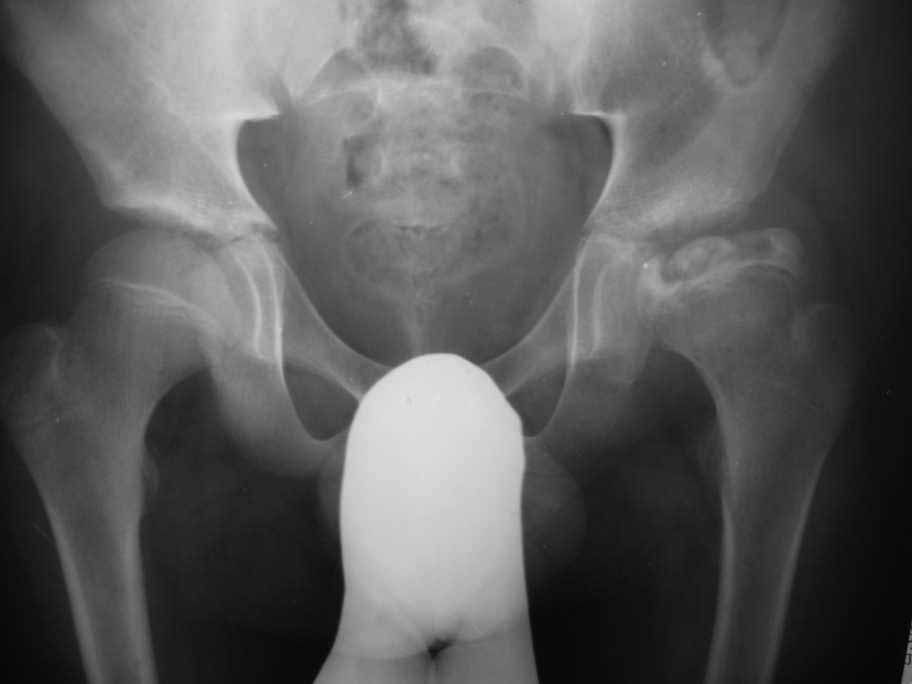

Болезнь Пертеса

Здравствуйте уважаемые коллеги, Посоветуйте, пожалуйста, тактику лечения для пациента с болезнью Пертеса.

Мальчик 14- ти лет обратился с жалобами на боли в левом тазобедренном суставе. Болеет около шести месяцев

Клинически : Движения в суставе ограничены ,сгибание 90 гр, отведение -30гр,ротационные движения 5-0-5 гр. Спасибо Ihor